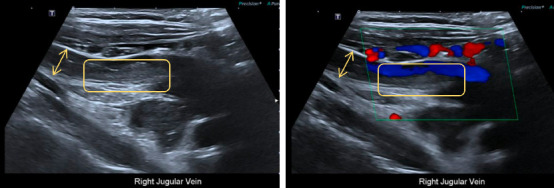

结核(TB),由结核分枝杆菌引起,主要影响肺部,但可以涉及几乎任何器官系统,表现为肺外结核。虽然结核病相关的高凝性和静脉血栓栓塞是公认的,但这种表现仍然不常见,诊断上具有挑战性,特别是在没有经典症状的情况下。病例介绍:我们报告一个24岁的免疫功能正常的女性谁最初提出无痛右侧颈部肿胀。影像显示右侧颈内静脉(IJV)出现急性血栓,原因不明。进一步检查显示纵隔淋巴结肿大坏死,怀疑为淋巴瘤。然而,患者后来出现癫痫发作,随后的神经影像学显示多发性颅内环增强病变。最终,纵隔镜淋巴结活检证实坏死性肉芽肿性炎症,结核聚合酶链反应(PCR)阳性,与弥散性结核累及血管和中枢神经系统一致。患者开始接受抗结核治疗、抗凝治疗和辅助皮质类固醇治疗,并安排多学科随访。讨论:本病例强调了结核病引起的高凝血性是孤立静脉血栓形成的潜在原因,并强调了结核病模拟恶性肿瘤时的诊断挑战。它还强调了即使在没有肺部症状的情况下,在鉴别诊断不明原因血栓形成和颅内病变时考虑结核病的重要性。结论:临床医生应在非典型血栓形成事件中保持对肺外结核的高度怀疑。早期组织诊断和多学科方法是有效管理和良好结果的关键。

Introduction: Tuberculosis (TB), caused by Mycobacterium tuberculosis, primarily affects the lungs but can involve virtually any organ system, manifesting as extrapulmonary TB. While TB-related hypercoagulability and venous thromboembolism are recognized, such presentations remain uncommon and diagnostically challenging, especially in the absence of classical symptoms. Case Presentation: We report the case of a 24-year-old immunocompetent female who initially presented with painless right-sided neck swelling. Imaging revealed an acute thrombus in the right internal jugular vein (IJV), with no clear underlying cause. Further evaluation showed enlarged necrotic mediastinal lymph nodes, raising suspicion for lymphoma. However, the patient later developed a seizure episode, and subsequent neuroimaging revealed multiple intracranial ring-enhancing lesions. Ultimately, mediastinoscopic lymph node biopsy confirmed necrotizing granulomatous inflammation, with a positive TB polymerase chain reaction (PCR), consistent with disseminated TB involving both vascular and central nervous systems. The patient was started on antitubercular therapy, anticoagulation, and adjunctive corticosteroids, with multidisciplinary follow-up arranged. Discussion: This case highlights TB-induced hypercoagulability as a potential cause of isolated venous thrombosis and underscores the diagnostic challenges when TB mimics malignancy. It also emphasizes the importance of considering TB in the differential diagnosis of unexplained thrombosis and intracranial lesions, even in the absence of pulmonary symptoms. Conclusion: Clinicians should maintain a high index of suspicion for extrapulmonary TB in atypical thrombotic events. Early tissue diagnosis and a multidisciplinary approach are key to effective management and favorable outcomes.